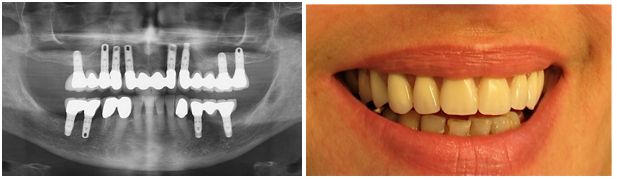

3/ Absence de toutes les dents

Classiquement, un édentement total est restauré au moyen d’une prothèse amovible complète. Si celle-ci est en général bien supportée à la mâchoire supérieure, il n’en va pas de même pour la prothèse inférieure. En effet cette prothèse peut être inconfortable et douloureuse du fait d’un manque de stabilité et elle peut représenter un véritable handicap.

La pose de deux ou de plusieurs implants recouverts de systèmes d’attaches type « boutons pressions » permet d’augmenter considérablement la tenue et le confort de la prothèse, laquelle est ainsi beaucoup mieux acceptée par le patient

La pose de plus d’implants permet même de restaurer l’arcade édentée au moyen d’un bridge fixe qui permet de supprimer les inconvénients liés à une prothèse amovible